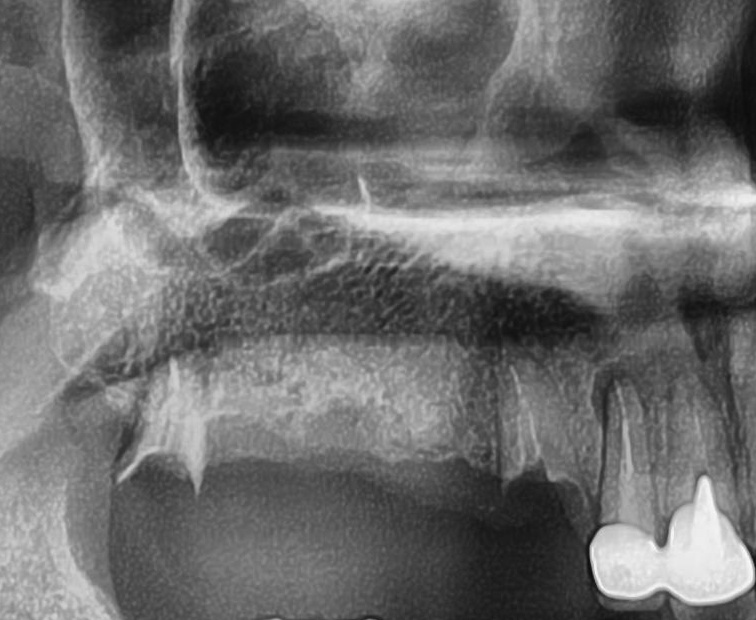

今回の患者様はインプラント植立を希望され、右上4番目・5番目・6番目・7番目の4本の植立が決まりました。